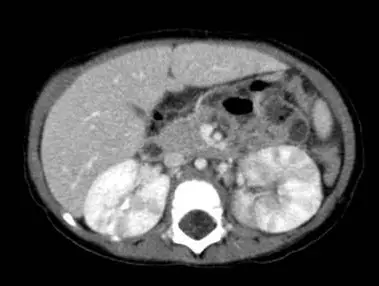

5歲女童高燒3日及膿尿(pyuria ; WBC 100~150/HPF),住院接受抗生素治療。經投與經驗性抗生素治療3日後,高燒並沒有改善。腹部電腦斷層(有注射顯影劑)檢查顯示如圖,女童最可能的診斷為:

橫斷面造影 CT 顯示:

- 右側腎(畫面左)實質均勻增強,形態正常。

- 左側腎(畫面右)中下極可見一楔形、由皮質向腎竇延伸的低密度區,邊緣不清,內部呈實質樣密度,未見圓形液化或厚壁環狀增強。

- 周圍脂肪層未顯著模糊,亦無明顯氣泡或腎周膿腫徵象。

此種「實質性、不液化、楔形低增強病灶」正是一典型 ALN 影像表現;若進一步壞死液化才會形成 renal abscess。